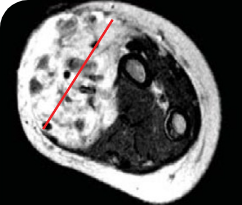

PEDIATRIC CANCER PATIENT WITH METASTATIC DISEASE

BASELINE BEFORE VITRAKVI

AFTER 6 MONTHS ON VITRAKVI

5-MONTH-OLD WITH INFANTILE FIBROSARCOMA5

PATIENT CASE:

INFANTILE FIBROSARCOMA

OF SOFT TISSUE1

- 5-month-old with IFSa

- Progression after chemotherapy

- Confirmed PRa after 4 cycles of VITRAKVI® (larotrectinib)

- Referred for definitive limb-sparing surgery after 6 cycles

of VITRAKVI; achieved pCRa,b

Clinical presentation1

- Diagnosed with localized IFS of the soft tissue of the forearm

Prior treatments and outcomes1

- Patient progressed after 2 cycles of vincristine and actinomycin D

- He was subsequently placed on vincristine, actinomycin D, and cyclophosphamide; however, his response remained inadequate to allow for limb-sparing surgery

Testing1

- ETV6a-NTRK3a fusion identified with DNAa NGSa panel testing

VITRAKVI treatment1

- VITRAKVI 100 mg twice daily orally

Response to VITRAKVI1

- Patient achieved a confirmed partial response after 4 cycles of VITRAKVI with a 45% reduction in tumor burden

- Following 6 cycles of VITRAKVI, the patient was referred for definitive limb-sparing surgery

- Pathology revealed a complete pathologic response and clear resection margins with scar tissue noted

Reduction in tumor burden1

MRIa imagery of the brain. Red line indicates the maximum dimension.1